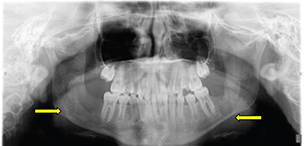

An 11-year-old female was referred by her dentist to our center’s oral maxillofacial surgeon to remove a jaw keratocyst, shown as a 2.5 × 2.5 cm radiolucent lesion of the right mandibular body (Figure 1: Dental Panorama X-ray). The patient was in sixth grade and enjoyed science and art.

Fig. 1. Panoramic dental radiograph showing multiple bilateral odontogenic keratocysts.